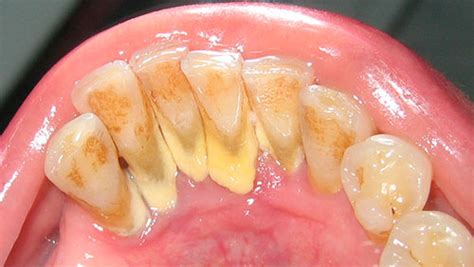

El sarro o cálculo dental es un agregado de bacterias, minerales y restos de comida que se deposita sobre los dientes. Se parece a los depósitos de cal que se acumulan en nuestras cocinas y baños. El residuo depositado sobre los dientes inflama las encías y provoca gingivitis y periodontitis.

El sarro dental es una capa de suciedad y residuos calcificados que se acumula en los dientes como consecuencia de una higiene oral insuficiente o ineficiente. Esta capa de suciedad también se puede amontonar en el borde o debajo de las encías, llegando a irritar los tejidos gingivales.

El sarro está colonizado por las bacterias de la cavidad oral o placa bacteriana, responsable a su vez de muchas de las patologías de los dientes y encías. El sarro en los dientes se forma por la acumulación progresiva de residuos de alimentos, proteínas salivares y restos microbianos, que se calcifican alrededor de las superficies de los dientes como consecuencia de la precipitación de las sales minerales y los iones presentes en la saliva.

El sarro se forma cuando la placa que no se ha eliminado con el cepillado y el uso de hilo dental se mineraliza con los minerales presentes en la saliva. La placa puede comenzar a endurecerse y convertirse en sarro en tan solo 24 a 72 horas después de la formación de la placa.